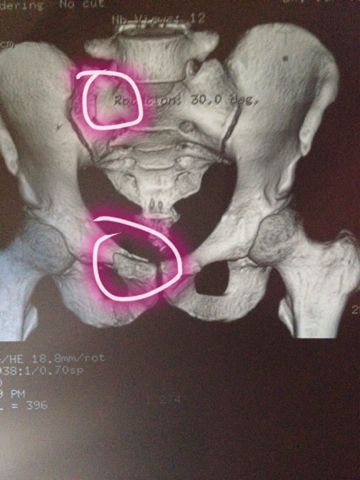

左侧坐骨支骨折图片

左侧坐骨支骨折图片,坐骨支骨图片

男,49岁,骨盆,双侧耻骨坐骨支骨折!